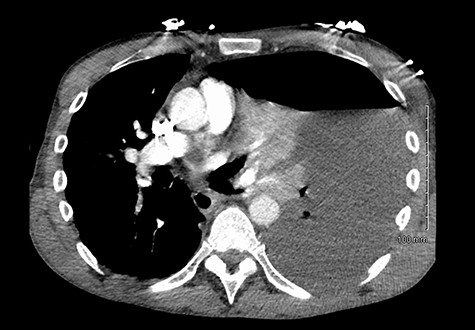

He maintained a high daily chest drain output of between 2.5 and 5 l. Upon recommencement of enteral feeding on day 3, we noticed an increase in opacity of the drainage fluid (Fig. 3). Normal triglyceride and chylomicron levels ruled out a chylothorax. Cultures from the drain eventually grew Enterococcus faecium, Candida albicans and Escherichia coli consistent with gut flora. At this point, an aerodigestive fistula was suspected. This was confirmed by a dye test subsequently performed with green ice cream, which tainted the drainage fluid green (Fig. 4). A repeat CT scan with oral and intravenous contrast delineated a fistula between the greater curvature of the stomach and the left basal pleura, with an extensive empyema (Fig. 5).